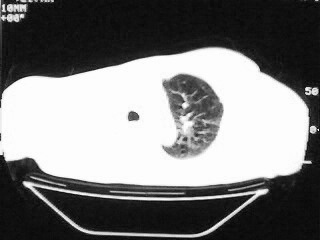

以下是引用随光逐影在2009-2-10 0:07:00的发言:[br]1)右肺放射性肺炎并节段性肺不张?请结合相关病史。2)右侧胸膜肥厚、粘连。3)心包膜增厚(或心包少量积液)。